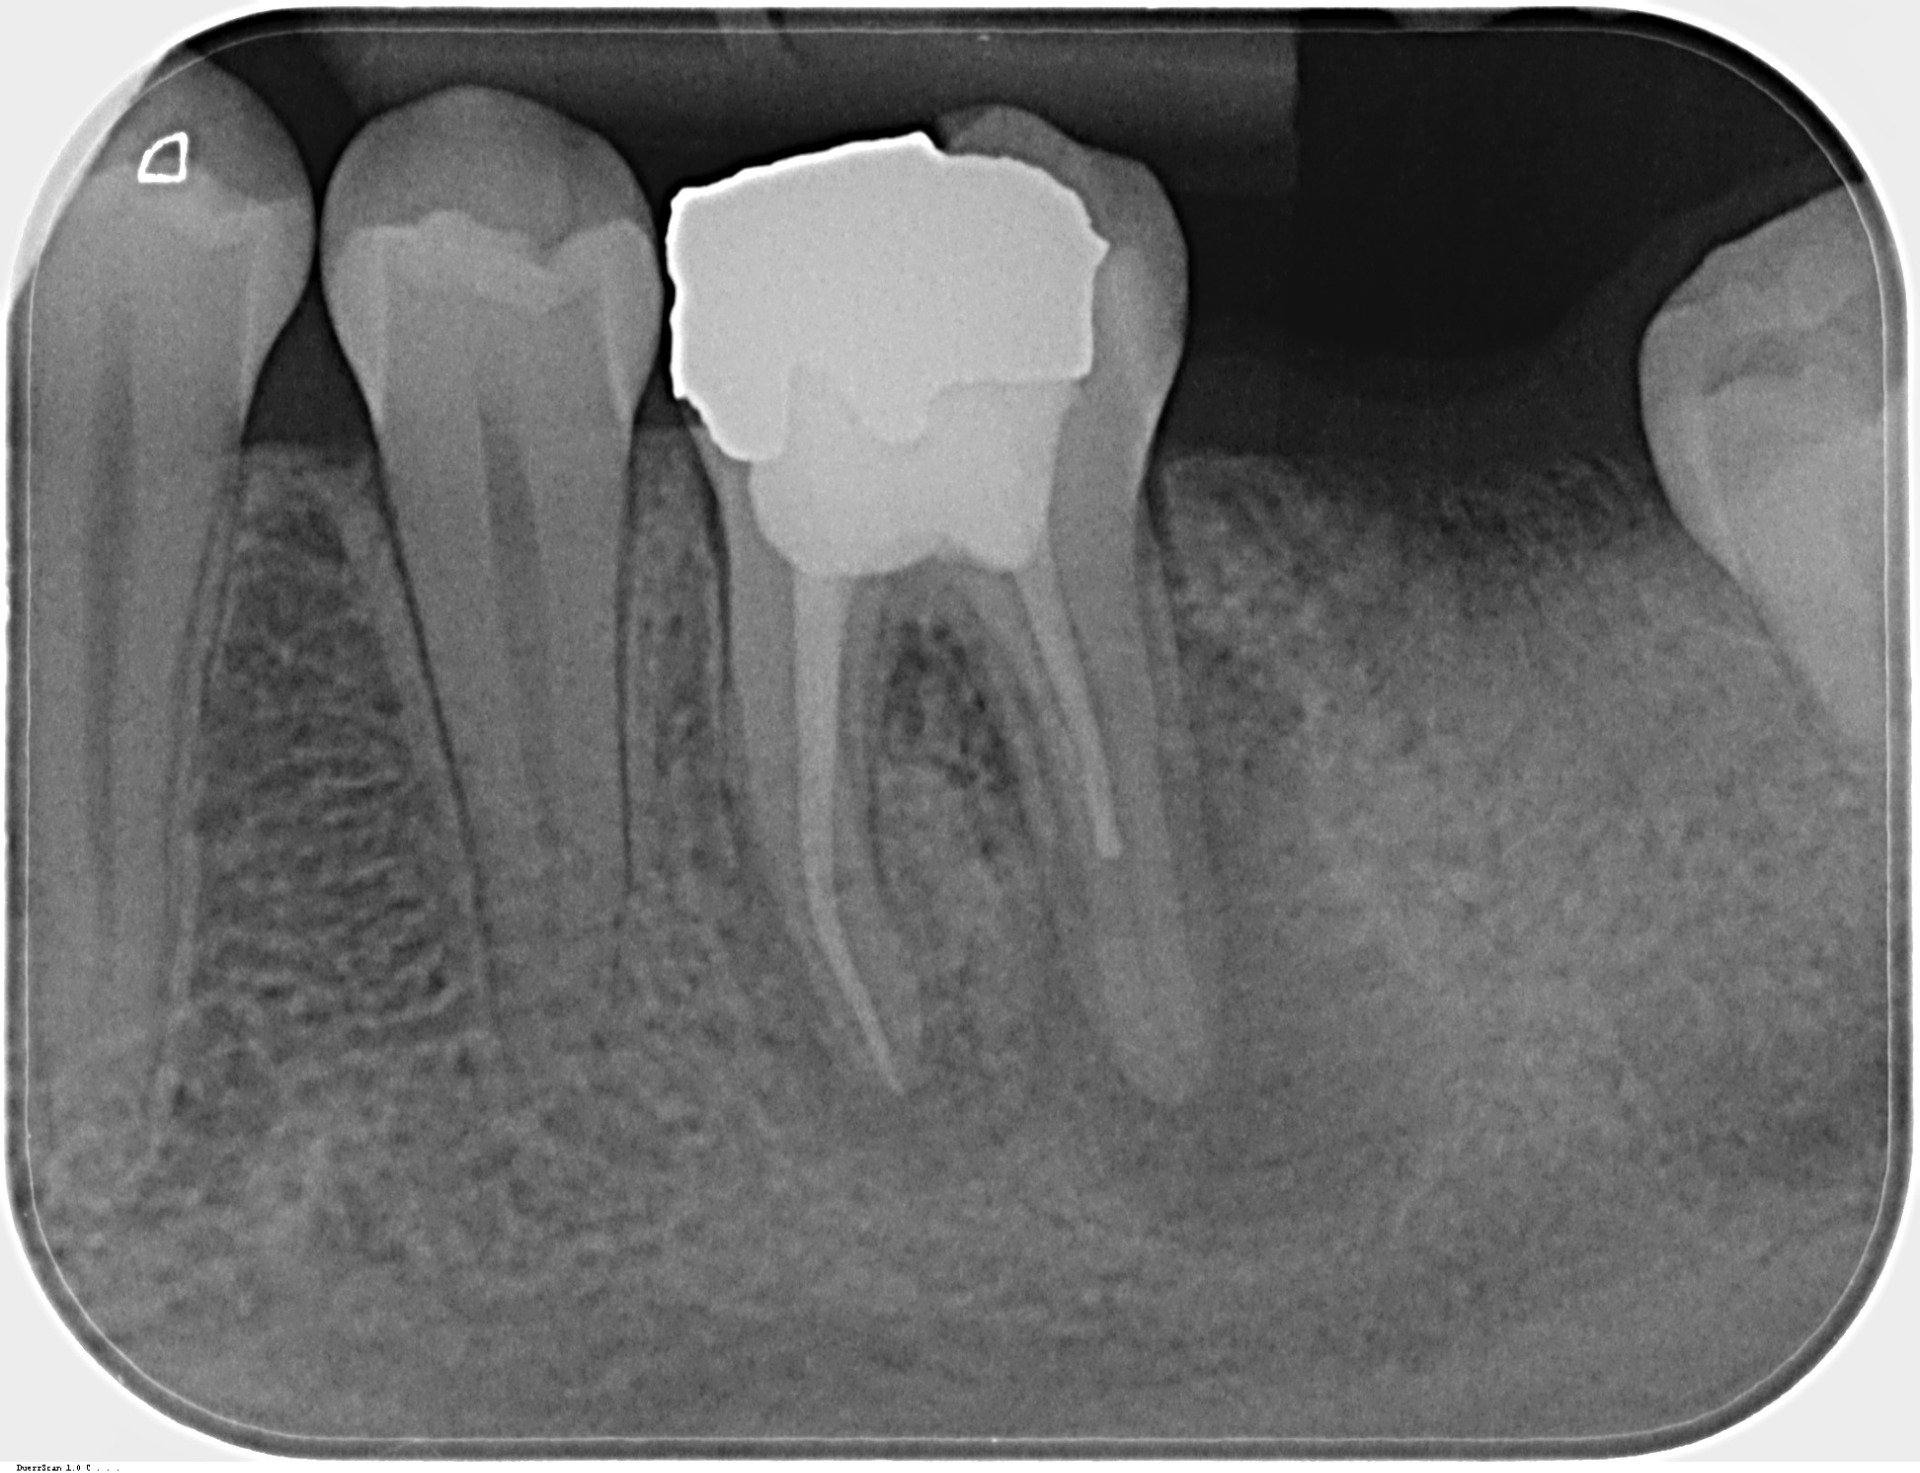

Zhojenie nálezu po 5 mesiacoch. MDDr. Gaľa